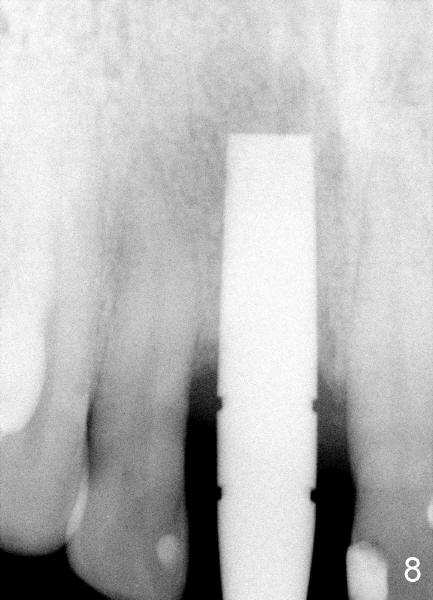

Two more weeks later, D2 implant (4.5x5.5x20 mm) is placed (Fig.9,10).  Fig.7 D2 thin socket former at ~ 16 mm depth, Fig.8 D2 medium socket former at ~ 19 mm.